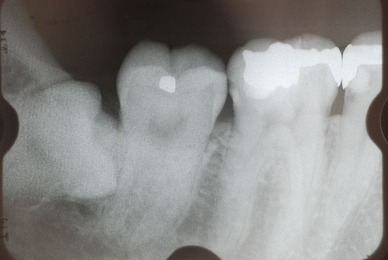

![0a9e48b6-s[1]](https://livedoor.blogimg.jp/netdental/imgs/4/0/40e1507e.jpg)